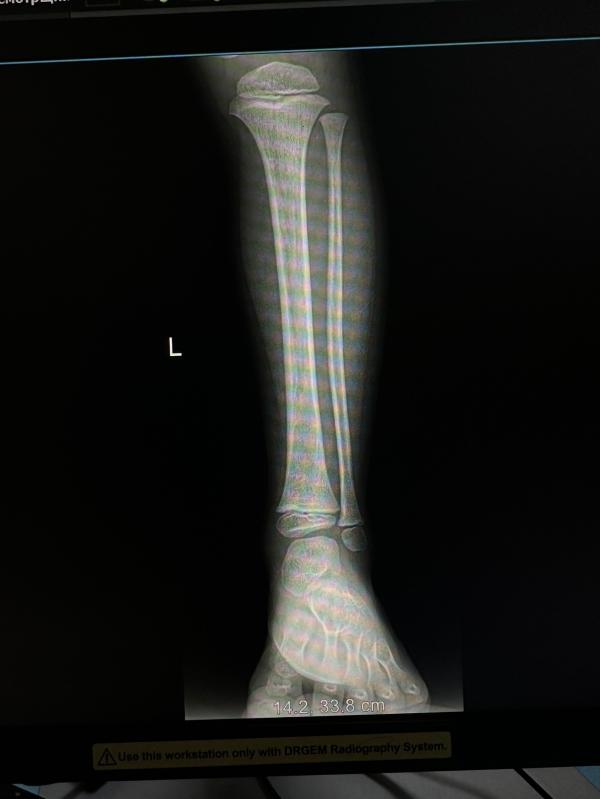

Старшый сын упал с турников,точнее спрыгнул неудачно.

Травматолог ничего не назначил. Ушиб.

Но ребенок не ходит. Передвигается на четвереньках.

А ходить больно говорит.